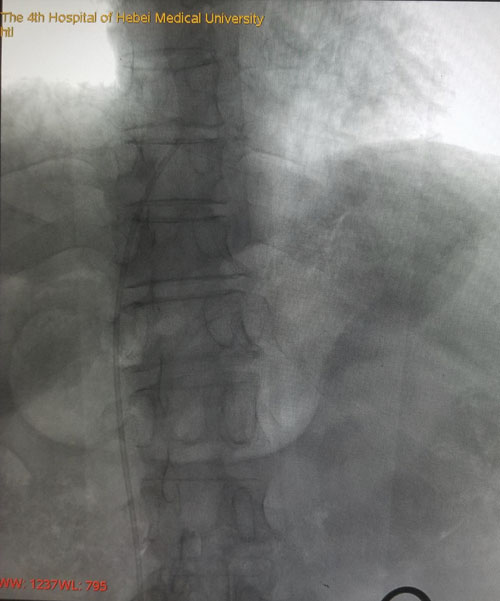

术后DSA评估导管尖端位置

本例患者由于是双侧乳腺癌术后伴双侧颈部及左胸壁广泛转移而来我院就诊,难以建立常规输液通路。乳腺中心回天立主管医生通过查阅大量文献资料并结合既往手术经验,与宋振川主任反复商讨后制定了股静脉港的置入方案。手术当日,在超声科纪晓惠主任、放射科杨光主任的协助下,成功将导管送达下腔静脉与右心房结合部,港座埋置于右下腹壁皮下,完成了我省首例股静脉穿刺静脉港置入术。术后第一天患者恢复顺利,下床活动良好,静脉通路顺畅。